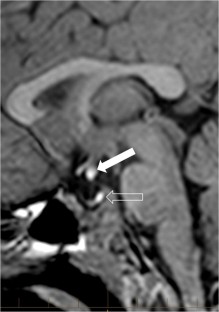

In six cases, two midline bright spots were identified on T1-weighted sequences obtained both with and without fat suppression. While one spot was located at the expected site of the neurohypophysis in the posterior sella, the second one was in the region of the median eminence, suggesting partial ectopic posterior pituitary gland. Growth hormone deficiency, either isolated (n=1) or combined with thyroid stimulating hormone deficiency (n=1) was found. None of the children had clinical signs of posterior pituitary dysfunction.